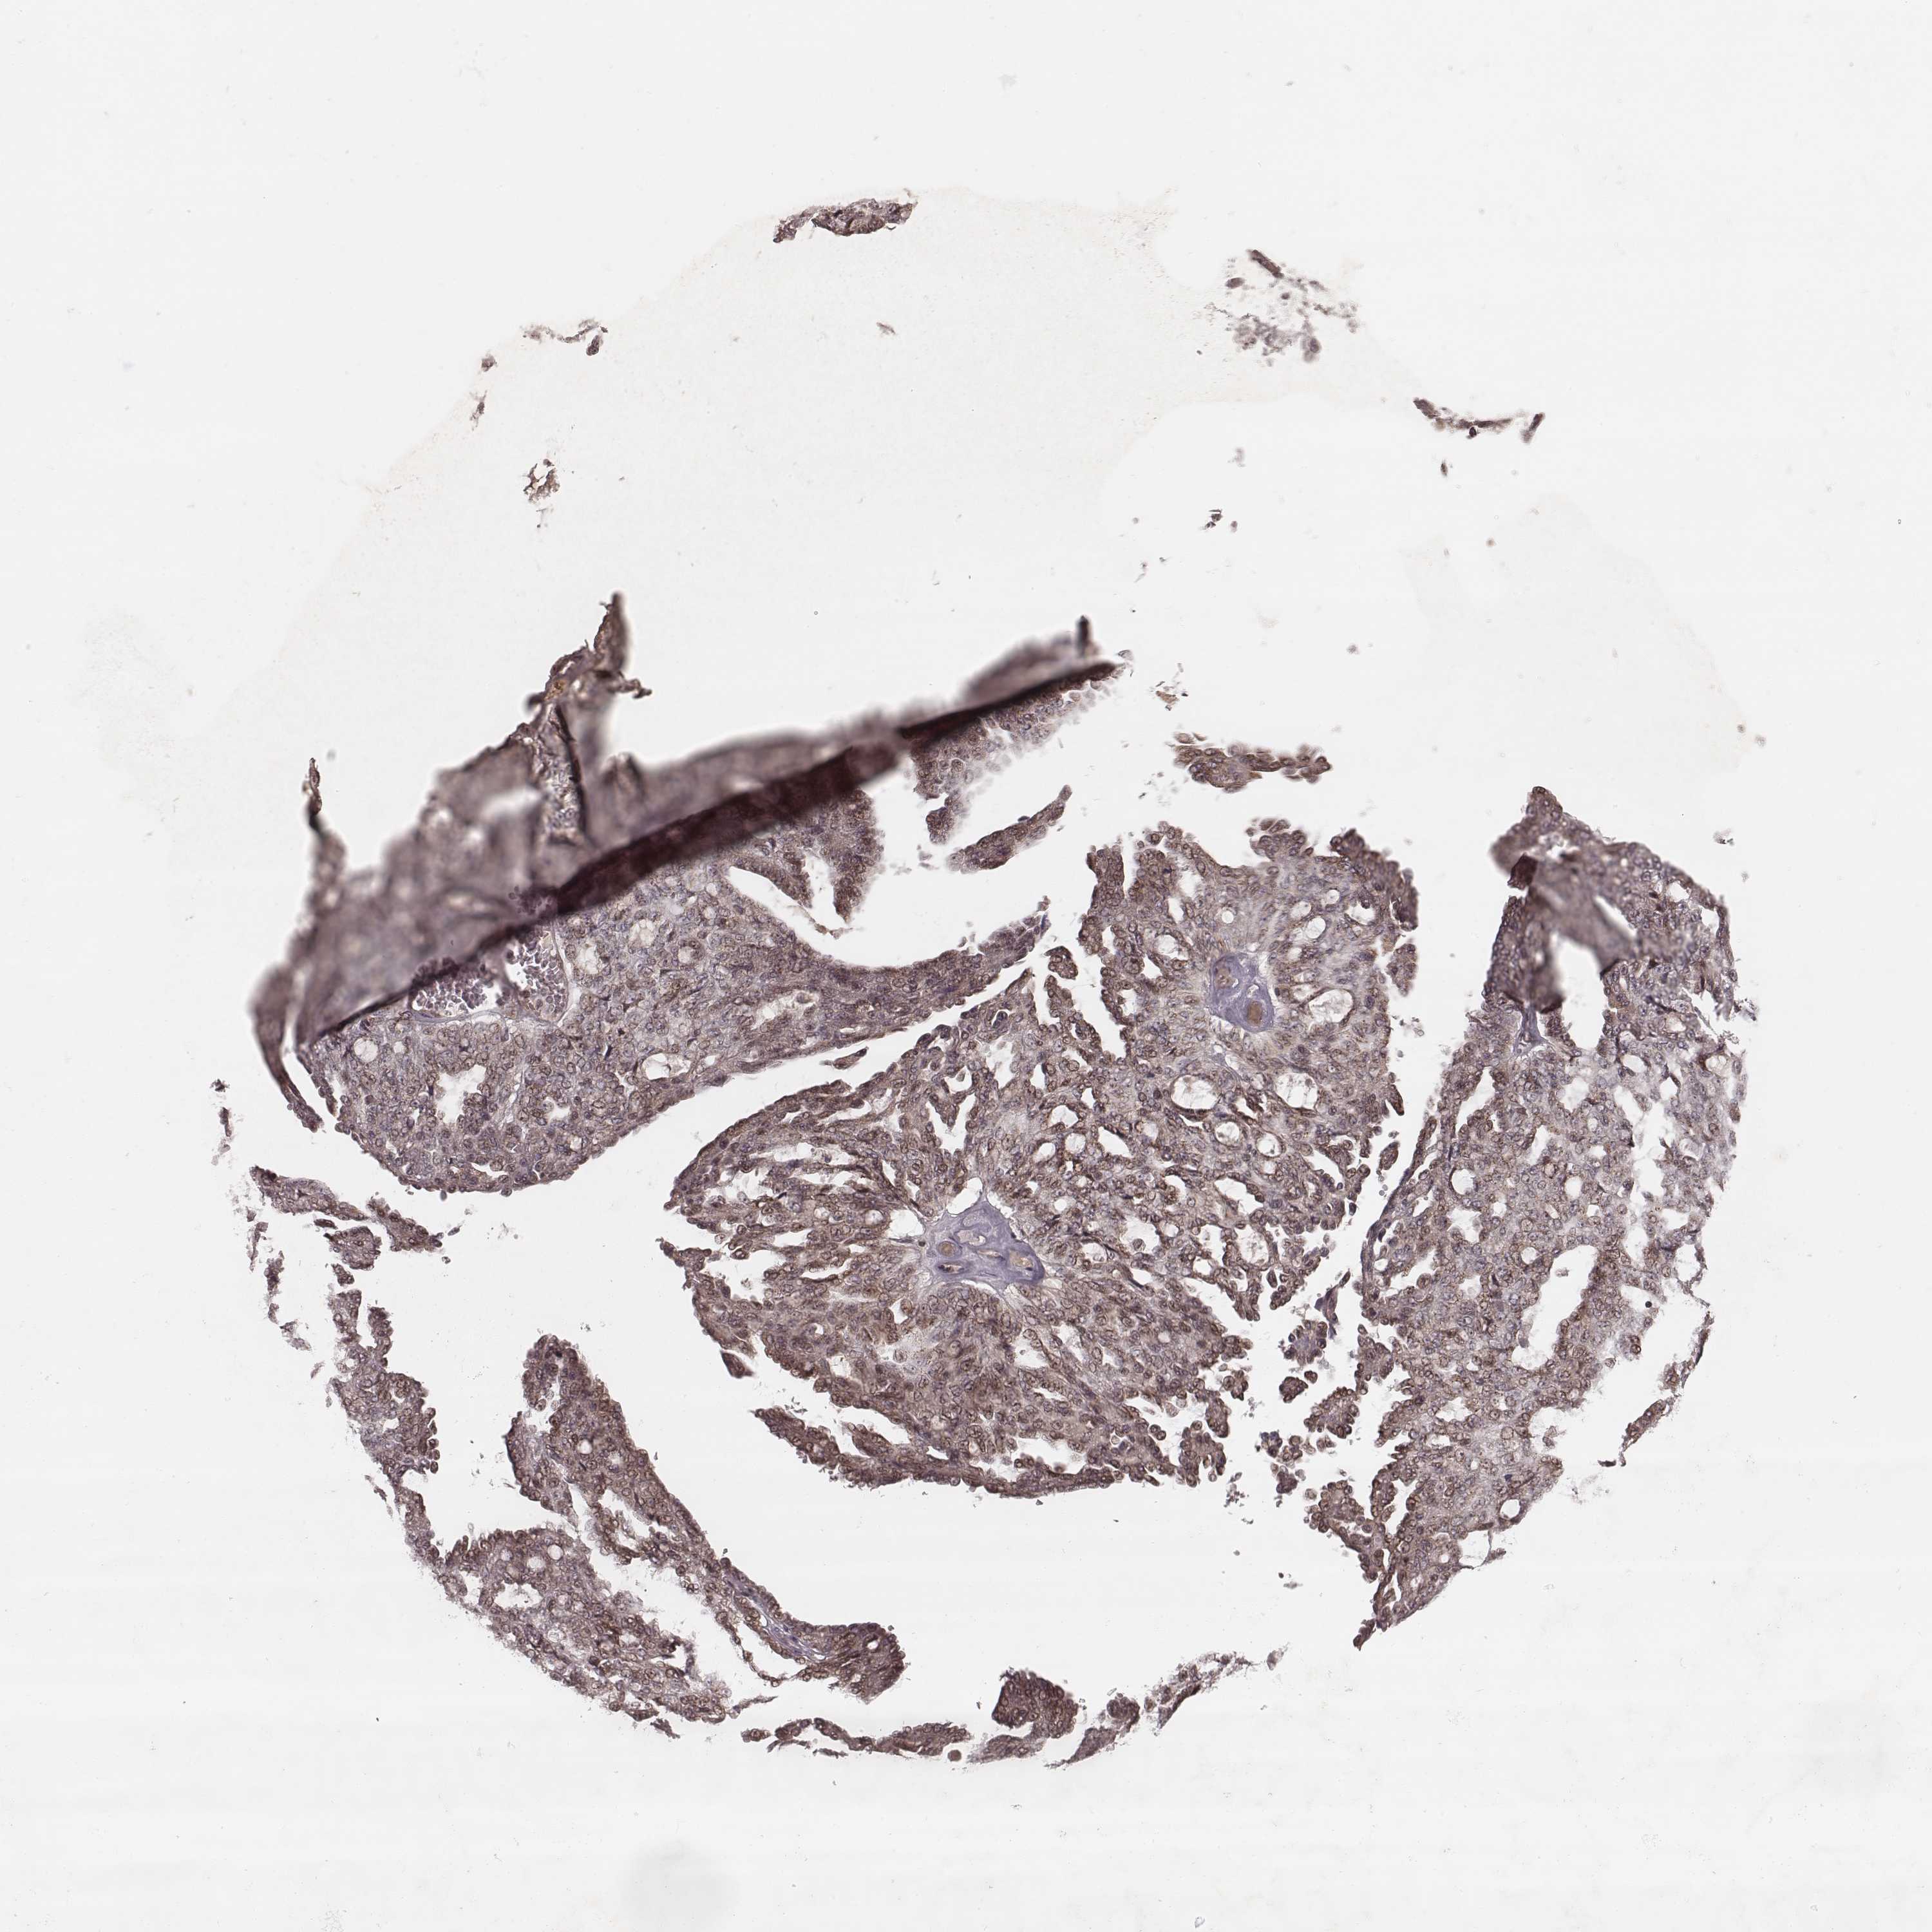

OVARIAN CANCER - Protein expressioni

A mouse-over function shows sample information and annotation data. Click on an image to view it in a full screen mode. Samples can be filtered based on level of antibody staining by selecting one or several of the following categories: high, medium, low and not detected. The assay and annotation is described here.

Note that samples used for immunohistochemistry by the Human Protein Atlas do not correspond to samples in the TCGA dataset.

Antibody stainingi

Antibody staining in the annotated cell types in the current human tissue is reported as not detected, low, medium, or high, based on conventional immunohistochemistry profiling in selected tissues. This score is based on the combination of the staining intensity and fraction of stained cells.

Each image is clickable and will lead to virtual microscopy that enables deeper exploration of all samples and also displays staining intensity scores, fraction scores and subcellular localization as well as patient and tissue information for each sample.

Antibody HPA059715

Staining

High

Medium

Low

Not detected

Intensity

Strong

Moderate

Weak

Negative

Quantity

>75%

75%-25%

<25%

None

Location

Nuclear

Cytoplasmic/membranous

Cytoplasmic/membranous,nuclear

Cystadenocarcinoma, serous, NOS

Cystadenocarcinoma, mucinous, NOS

Carcinoma, endometroid